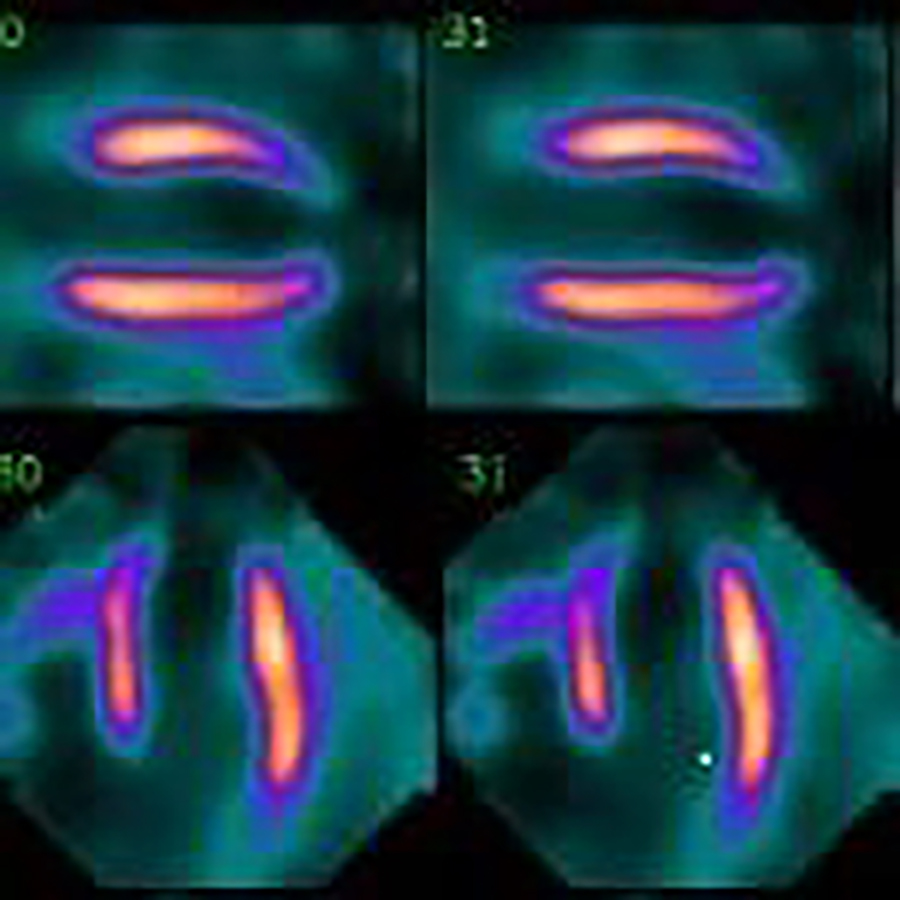

心筋血流シンチグラフィー

血液が心筋各部位へ正常に流れているかを診る検査です。心筋梗塞や狭心症などの早期発見や治療経過を知るのに有用です。

当院で稼働しているD-SPECT装置は検出器に半導体を使った心臓専用ガンマカメラで、京都府内では当院が初めての導入です。(写真3)

従来のガンマカメラと比べ感度・分解能が向上しています。感度が向上することで20~30分程度必要だった撮影時間が5~10分に短縮されました。また分解能が向上することで画像がより鮮明で良質な画像を得ることができるようになりました。(図4)

従来は回転していた検出器は固定され、両手を拳上し仰臥位で行っていた撮影が自然に座った姿勢で行えます。患者さんには安全でリラックスして検査を受けていただけます。